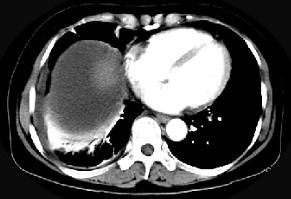

问题 女,59岁,发热、右上腹痛、右下肺呼吸音低,影像检查如图,最可能诊断是 ( )

选项 A、肝硬化腹水 B、大网膜膈下间位 C、膈下脓肿 D、肝包膜下出血 E、腹腔积液

答案 C